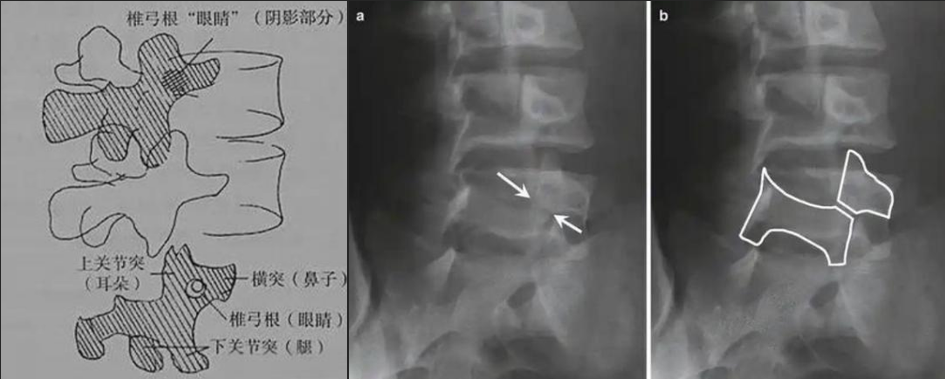

腰椎斜位片看什么?

如果说腰椎正侧位片是常规检查体位,那么腰椎斜位片就是给腰椎的某个零件一张特写镜头,这个特殊且关键的部位就是椎弓根峡部。

图a和图b 腰椎斜位:狗脖“戴项圈征”,诊断椎体椎弓峡部裂

椎弓根峡部是椎体后部椎弓上最狭窄、最薄弱、但应力最集中的部位,在常规腰椎X线正侧位上,因腰椎其他结构的重叠显示不清,但是在腰椎斜位上,能够清楚完美地展现出来,若其在斜位片上表现为不连续,则可诊断为椎弓根峡部裂,即腰椎的关键承重部分的骨质断裂,这是导致青少年和运动员腰痛的主要原因。

在腰椎斜位片上,腰椎的附件结构形成了一个经典的“斯科蒂狗”图案,其中“狗脖子”处即代表椎弓根峡部,若“狗脖子”上出现了一条透亮清晰的线,就像给狗戴了一条“项链”,即“戴项圈征”,这是诊断椎弓峡部裂的直接证据。